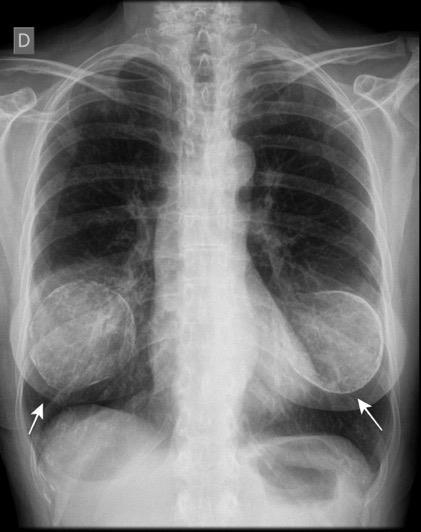

Prótesis

Sombra “simétrica y de densidad “uniforme” de las mamas

Prótesis de ambas mamas densamente calcificadas

Ocurren en 10% de los implantes de mama.

En los 3 años después del implante.